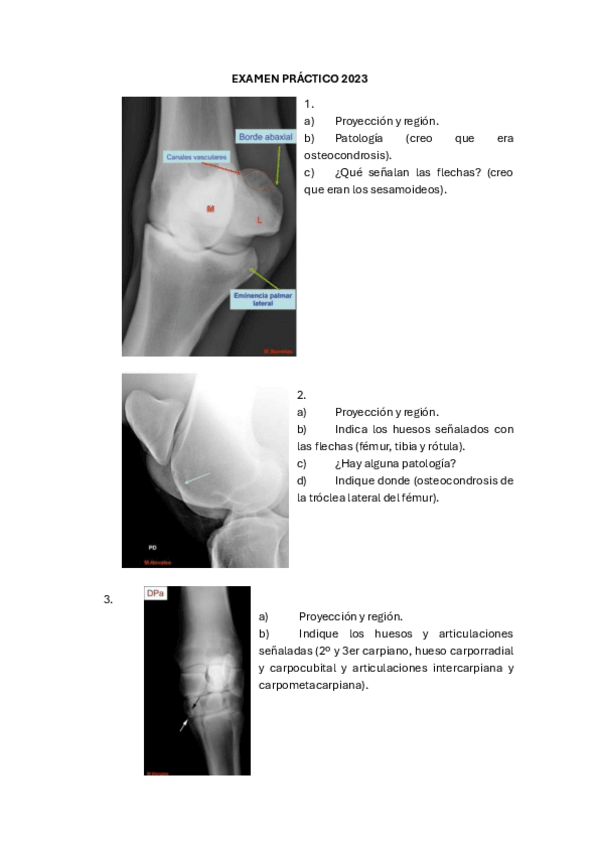

Exámenes - examenes-practico-dx.pdf

6 páginas